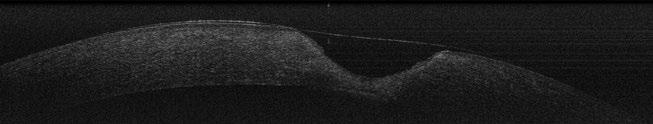

Utilidad clínica de la ecografía pulmonar y cardiaca en urgencias